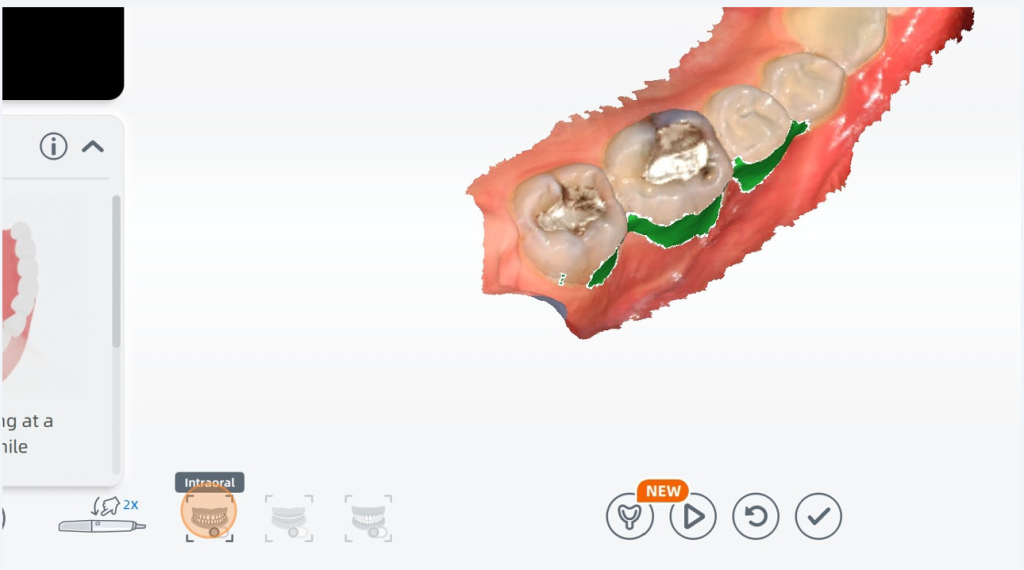

My scan had some artifacts from scanning without AI on, I can remove it easily by clicking the remove isolated data button.

Any areas marked in green can be filled in with scan data by unpausing your scanner and scanning over the area again.